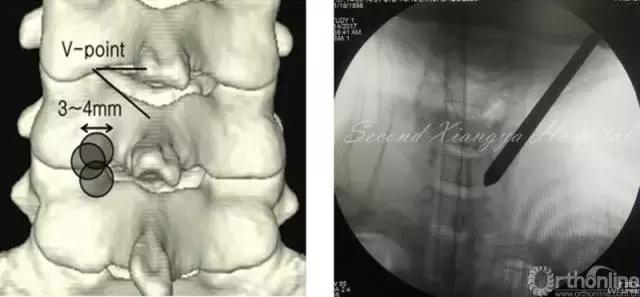

颈椎后路锁孔:颈椎后路结构单一,穿刺的靶点指向病变节段上椎板下缘、关节突和下椎板上缘组成的“V”点偏外骨性结构,穿刺端避免偏内落入椎管误伤脊髓。

颈椎后路经椎间孔入路骨性标志点为“V”点,操作时注意“靶区触骨,动力先行,显根上下,脊髓勿碰。”也就是说,建立靶区应落到V点骨性结构部分,再用动力沿V点磨除外层皮质骨,黄韧带边缘会自然显露,再用Kerrison钳扩大显露神经根肩部与腋部,用神经勾进行探查和髓核摘除,手术全程都要注意保护脊髓,避免通过后方进行椎间隙髓核摘除这一危险操作。